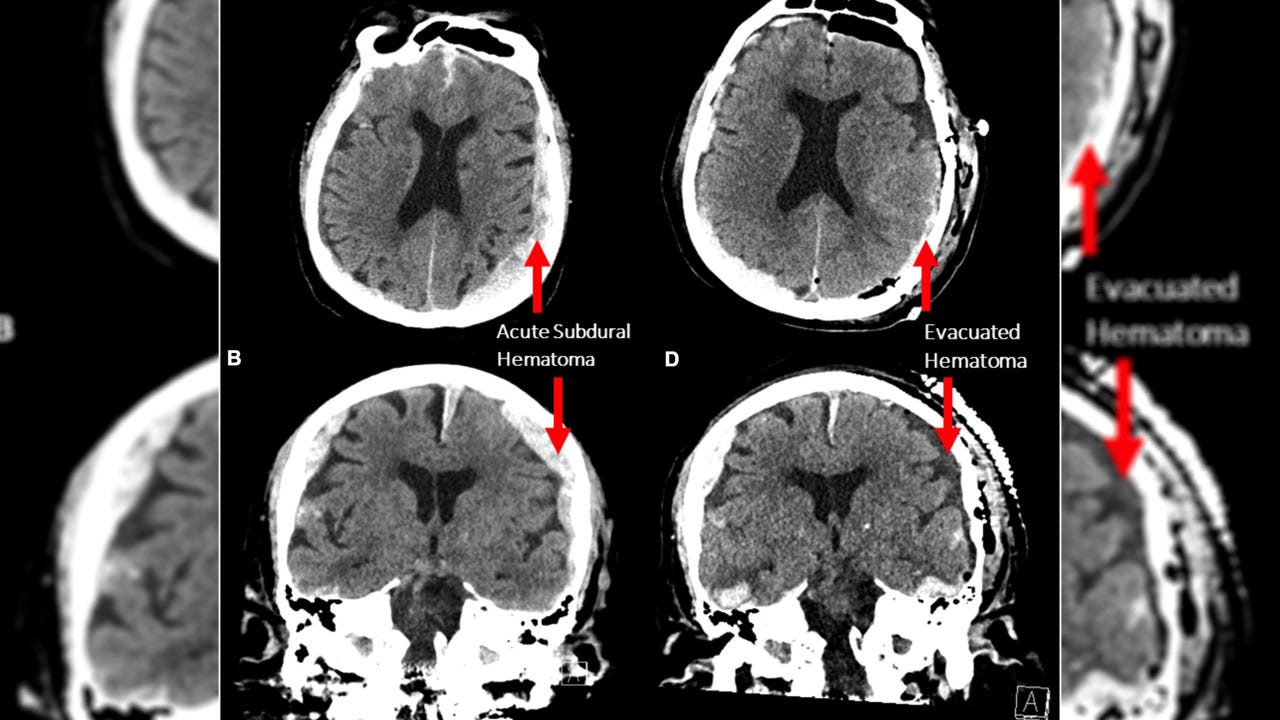

16x9 photo 0 study brain scans

Pictured are CT scans of the patient, whose identity was not disclosed. (Credit: Front. Aging Neurosci., / Provided)